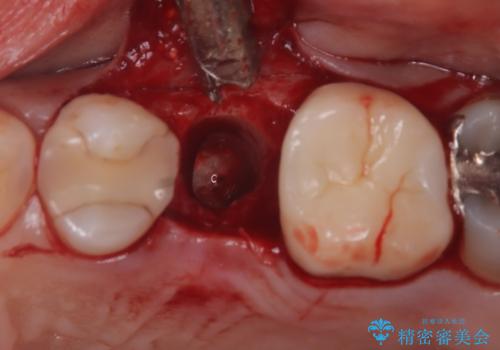

重度の歯周病により保存困難と診断し、抜歯後にインプラント治療を行いました。

抜歯後十分な骨の回復が認められず、単独の骨増生を行った後にインプラントを埋入しました。